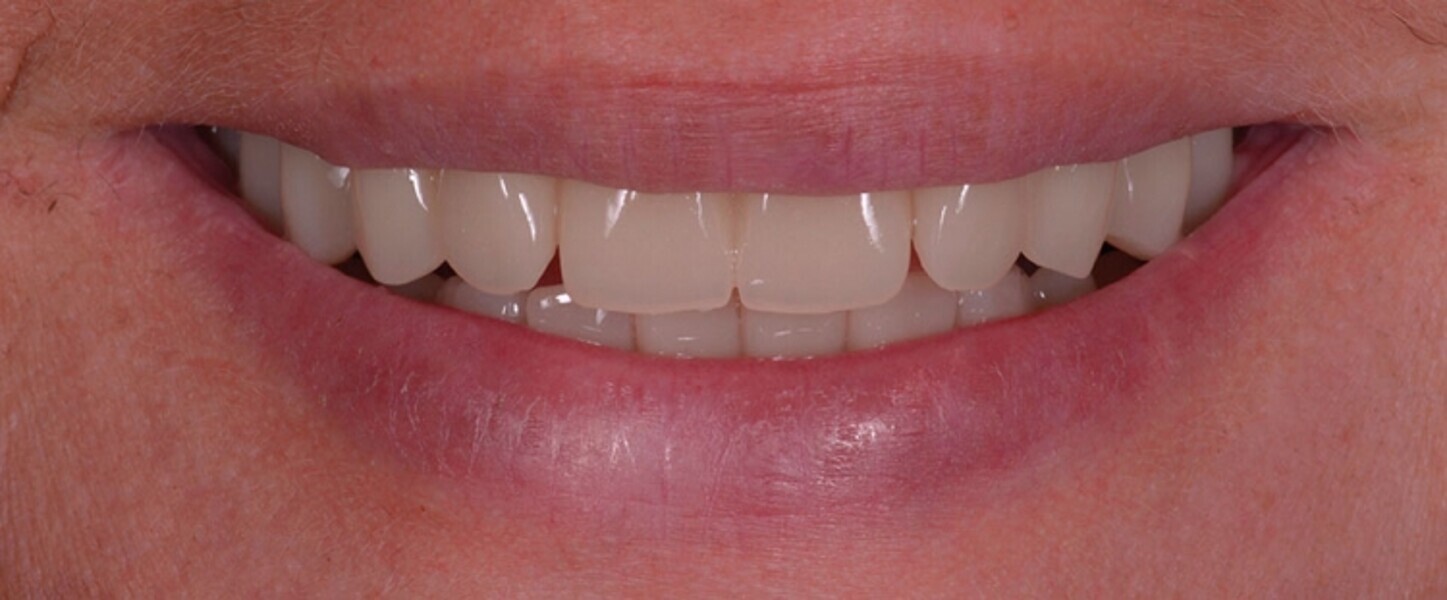

Protocollo SKY fast & fixed